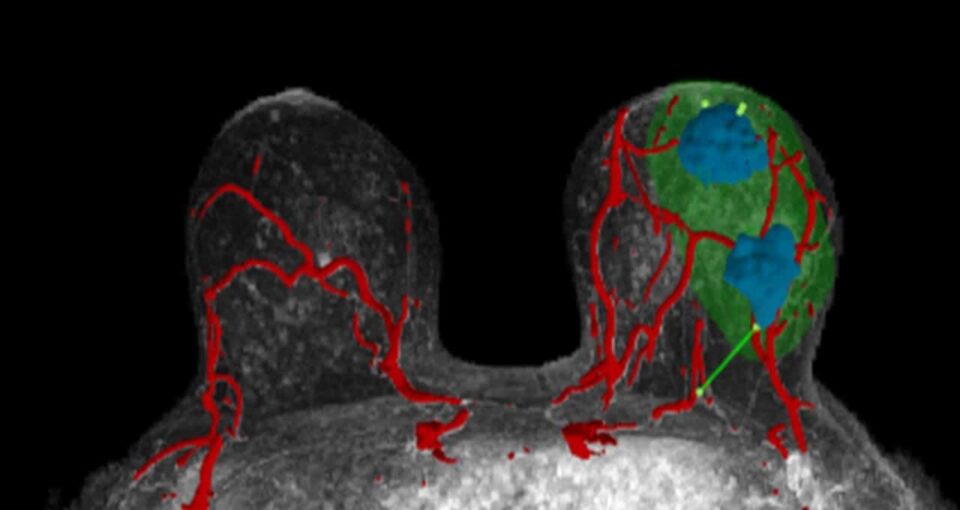

Supporting Surgeons

Illinois-based startup SimBioSys has created TumorSight Viz, a technology that converts MRI images into 3D models of breast tissue. This helps surgeons better treat breast cancers by providing detailed visualizations of tumors and surrounding tissue.